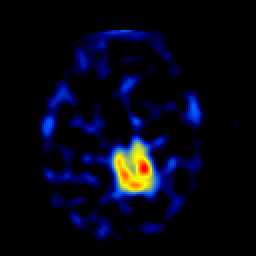

SPECT TL Study #4 -- Slice #35

[Home][Help][Clinical][Tour 1][Tour 2][Tour 3] Slice 35